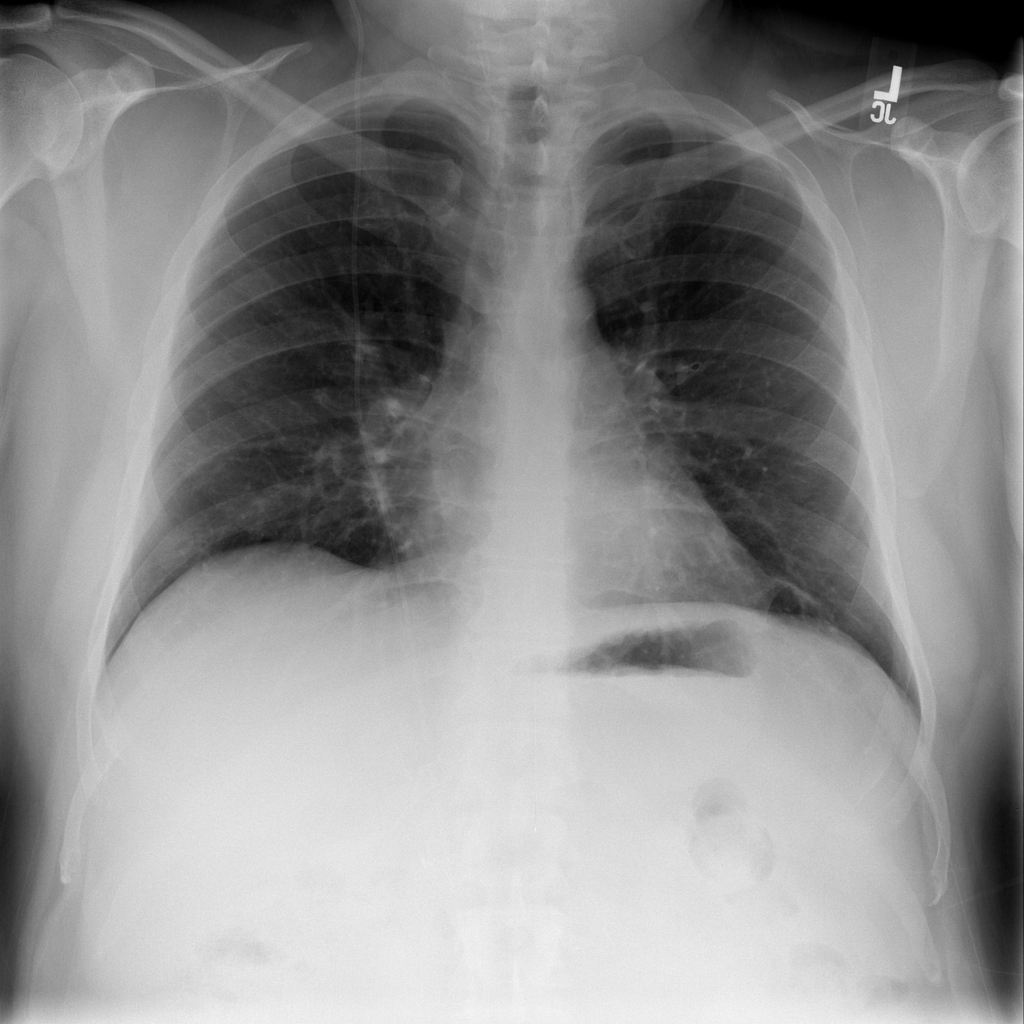

Consolidation

Consolidation refers to air-space filling that makes part of the lung appear denser on imaging.

Showing up to 90 reference images for Consolidation.

PAT-C1A7 · IMG-055Consolidation

PAT-C1A7 · IMG-055

AP